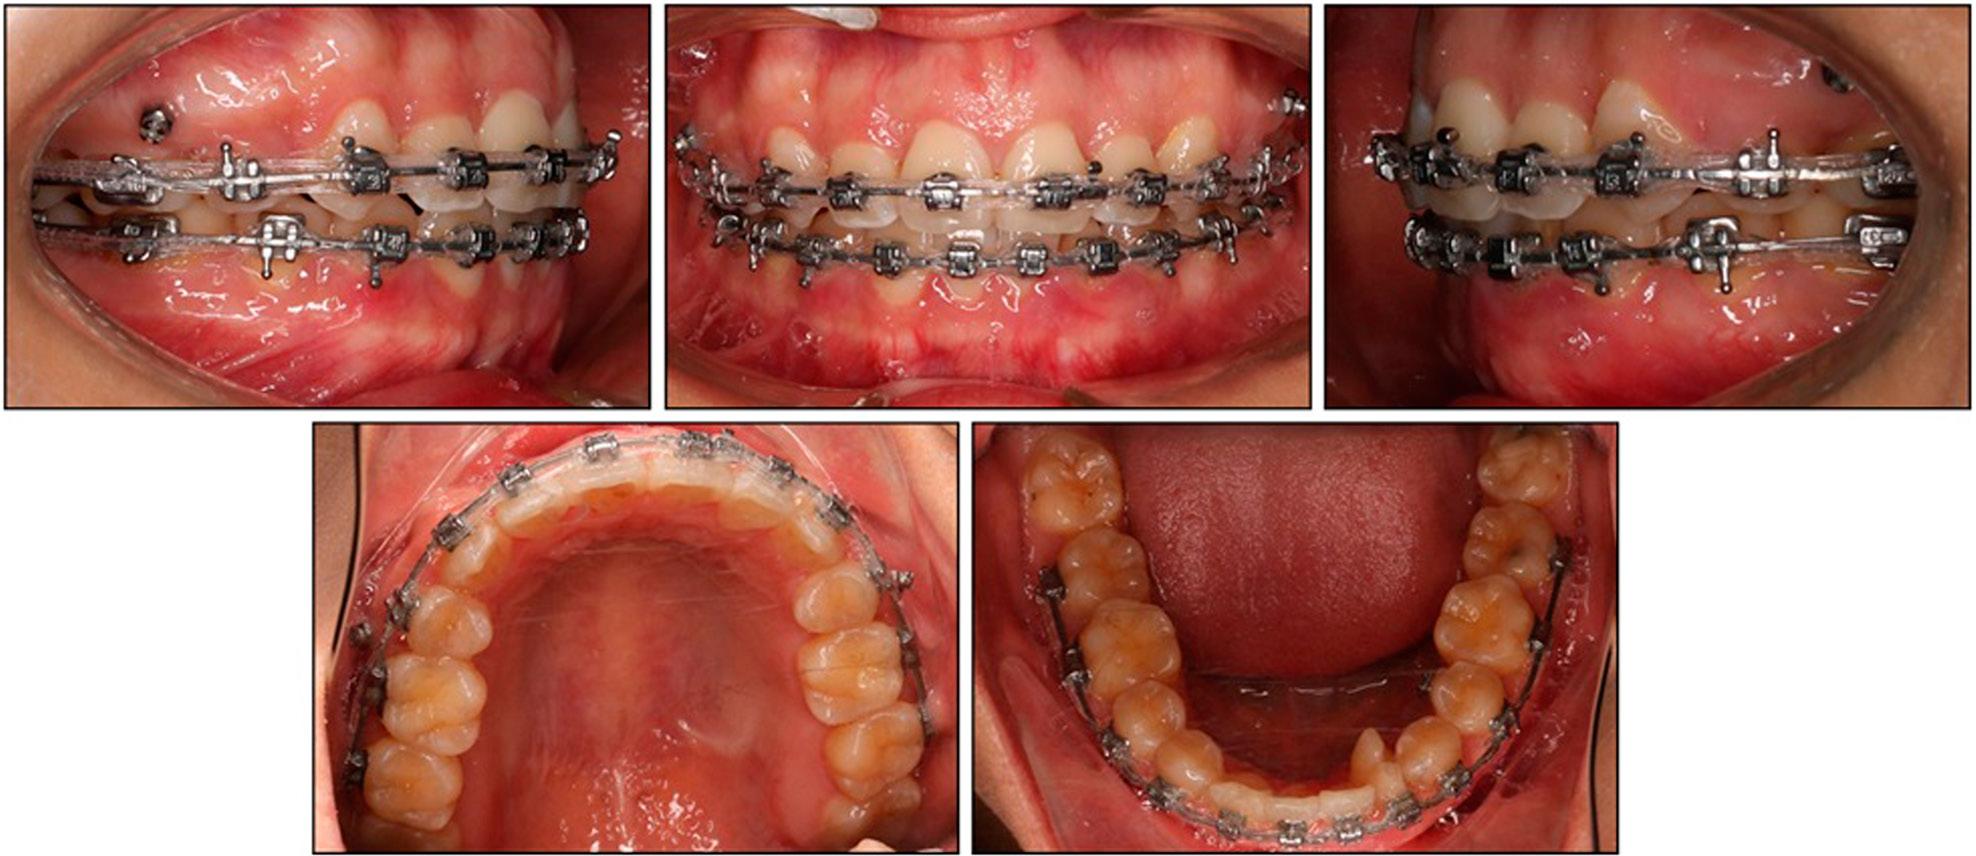

Intra-orally, a stable bilateral Angle Class I molar and functional “canine” relationship was achieved (Figure 6). The mandibular dental midline was successfully moved to the left to co-incide with the maxillary and facial midlines. Overjet finished at 2.6 mm and overbite at 2.3 mm, both of which were within normal limits, and the severe maxillary crowding was resolved. The rotated left fused tooth aligned harmoniously with its neighbours, and the arch forms were well co-ordinated.

A cephalometric evaluation confirmed that the skeletal base remained essentially unchanged (SNA 83.0°, SNB 79.0°, ANB 4.0°), while vertical control was preserved (FMA 33.8°). Dentally, the maxillary incisors were uprighted by almost 8° (U1-SN, 98.9°) and retracted 3.7 mm relative to NA; the mandibular incisors were tipped lingually by 5.5° (IMPA, 84.4°), increasing the inter-incisal angle from 120.8° to 134.8°. These movements accounted for the reduction in lip prominence and the improvement in smile aesthetics (Figure 7).